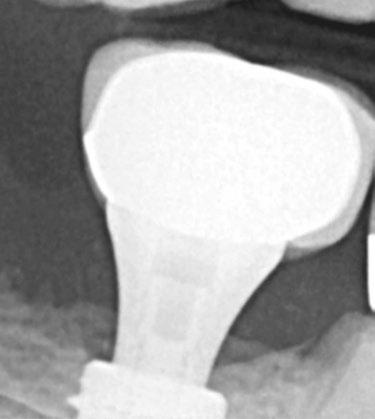

Judy McIntyre, DMD, MS Figure 1: Acutely curved and calcified buccal canal right under upper left premolar crown margin; valuable information for access and management. No. 9 also has a PARL, which was only incidentally captured Figure 2: Large PARL with destruction of the maxillary sinus floor and sinusitis as a result

About 10 years after completing residency, I opened my own practice and invested in a DEXIS CBCT. Initially, I only used it for apicoectomies and retreatments. In time, I began to realize how helpful it was for all my cases. With the 3D-scan information (Figure 1), I could have saved myself some humbling experiences and surprises. Endodontists hate surprises, and we really hate failures! Once I started using my CBCT more frequently, I was able to appreciate things that would have otherwise been intra-op surprises and plan for them prior to starting the procedure. The 3D data allows me to properly assess prognosis, determine the best course of treatment, and plan that treatment with a level of precision that is impossible otherwise.